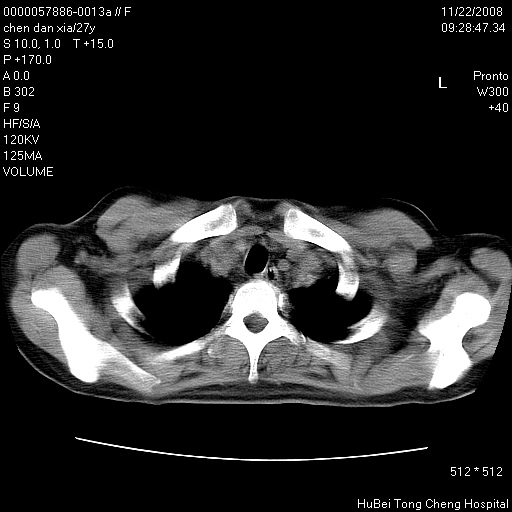

标题: CT16752:F,27Y。发热咳嗽20余天,伴盗汗。 [打印本页]

标题: CT16752:F,27Y。发热咳嗽20余天,伴盗汗。

建议强化观察,考虑肺门及纵隔淋巴结结核。另外还需结合实验室检查。

气管前腔静脉后淋巴结肿大 右肺门纹理模糊

淋巴结核?

右下肺纹理模糊;纵隔可见肿大淋巴节;右心缘旁结节,边缘光滑,纵隔窗病变范围较肺窗明显小,首先考虑右下肺结核,不排外淋巴瘤

下肺结节,结节内钙化,肺门纵隔淋巴肿大 结核可能性大

气管旁,两肺门可疑淋巴结肿大,建议ct增强.